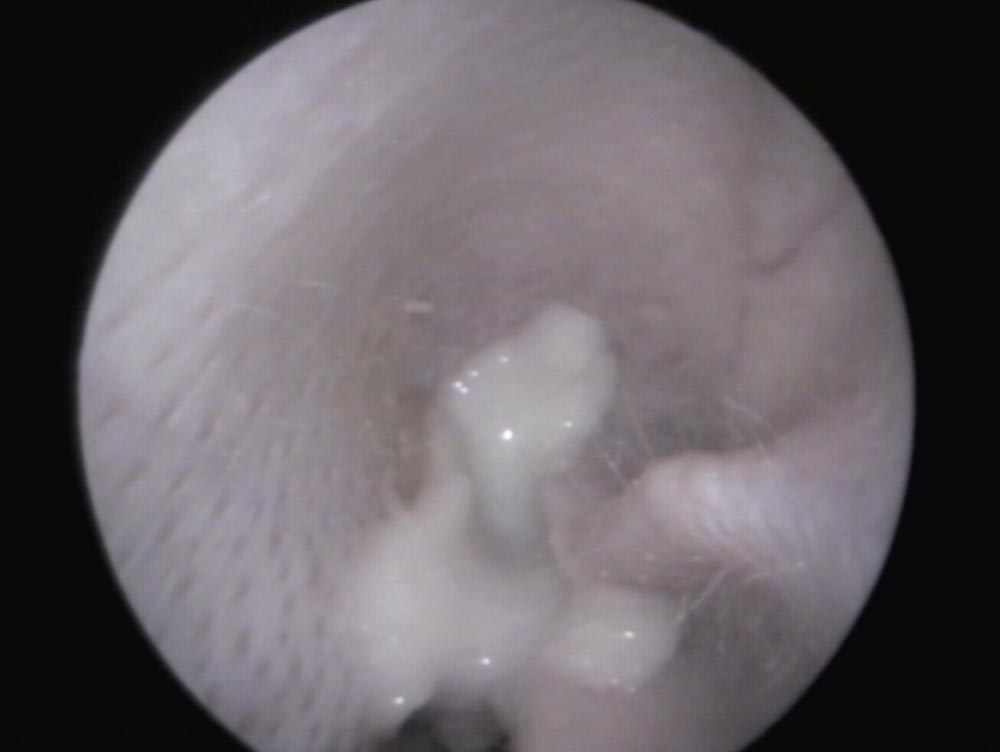

Der äußere Gehörgang wird mittels Otoskop/Videoendoskop untersucht. Bei einem gesunden Ohr kann man, durch leichten Zug der Pinna nach oben (Abb. 1), in der Regel bis zum Trommelfell sehen (Abb. 3). Ist Material im Ohrkanal vorhanden, gilt es zu unterscheiden, ob es „nur“ gestautes Zerumen (weiß in Tiefe, gelblich zur Öffnung hin) und der Gehörgang sonst reizlos ist, oder ob Entzündungszeichen (Rötung, Schwellung, Läsionen, Verflüssigung des Sekrets) (Abb. 4) und mögliche Primärursachen wie Fremdkörper und/oder Ektoparasiten vorhanden sind. Bei der Unterscheidung hilft die Zytologie.

Abb. 4: Blick in ein mit Eiter gefülltes Außenohr eines Kaninchens – das sonst reizlose Außenohr spricht für die Herkunft des Eiters aus dem Mittelohr

Bildquelle: J. Hein